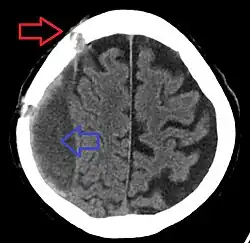

| Subdural hematoma as marked by the arrow with significant midline shift | |

Subdural hematomas occur most often around the tops and sides of the frontal and parietal lobes.[3][2] They also occur in the posterior cranial fossa, and near the falx cerebri and tentorium cerebelli.[3] Unlike epidural hematomas, which cannot expand past the sutures of the skull, subdural hematomas can expand along the inside of the skull, creating a concave shape that follows the curve of the brain, stopping only at dural reflections like the tentorium cerebelli and falx cerebri.

On a CT scan, subdural hematomas are classically crescent-shaped, with a concave surface away from the skull. However, they can have a convex appearance, especially in the early stages of bleeding. This may cause difficulty in distinguishing between subdural and epidural hemorrhages. A more reliable indicator of subdural hemorrhage is its involvement of a larger portion of the cerebral hemisphere. Subdural blood can also be seen as a layering density along the tentorium cerebelli. This can be a chronic, stable process, since the feeding system is low-pressure. In such cases, subtle signs of bleeding—such as effacement of sulci or medial displacement of the junction between gray matter and white matter—may be apparent.

Fresh subdural bleeding is hyperdense, but becomes more hypodense over time due to dissolution of cellular elements. After 3–14 days, the bleeding becomes isodense with brain tissue and may therefore be missed.[20] Subsequently, it will become more hypodense than brain tissue.[21]